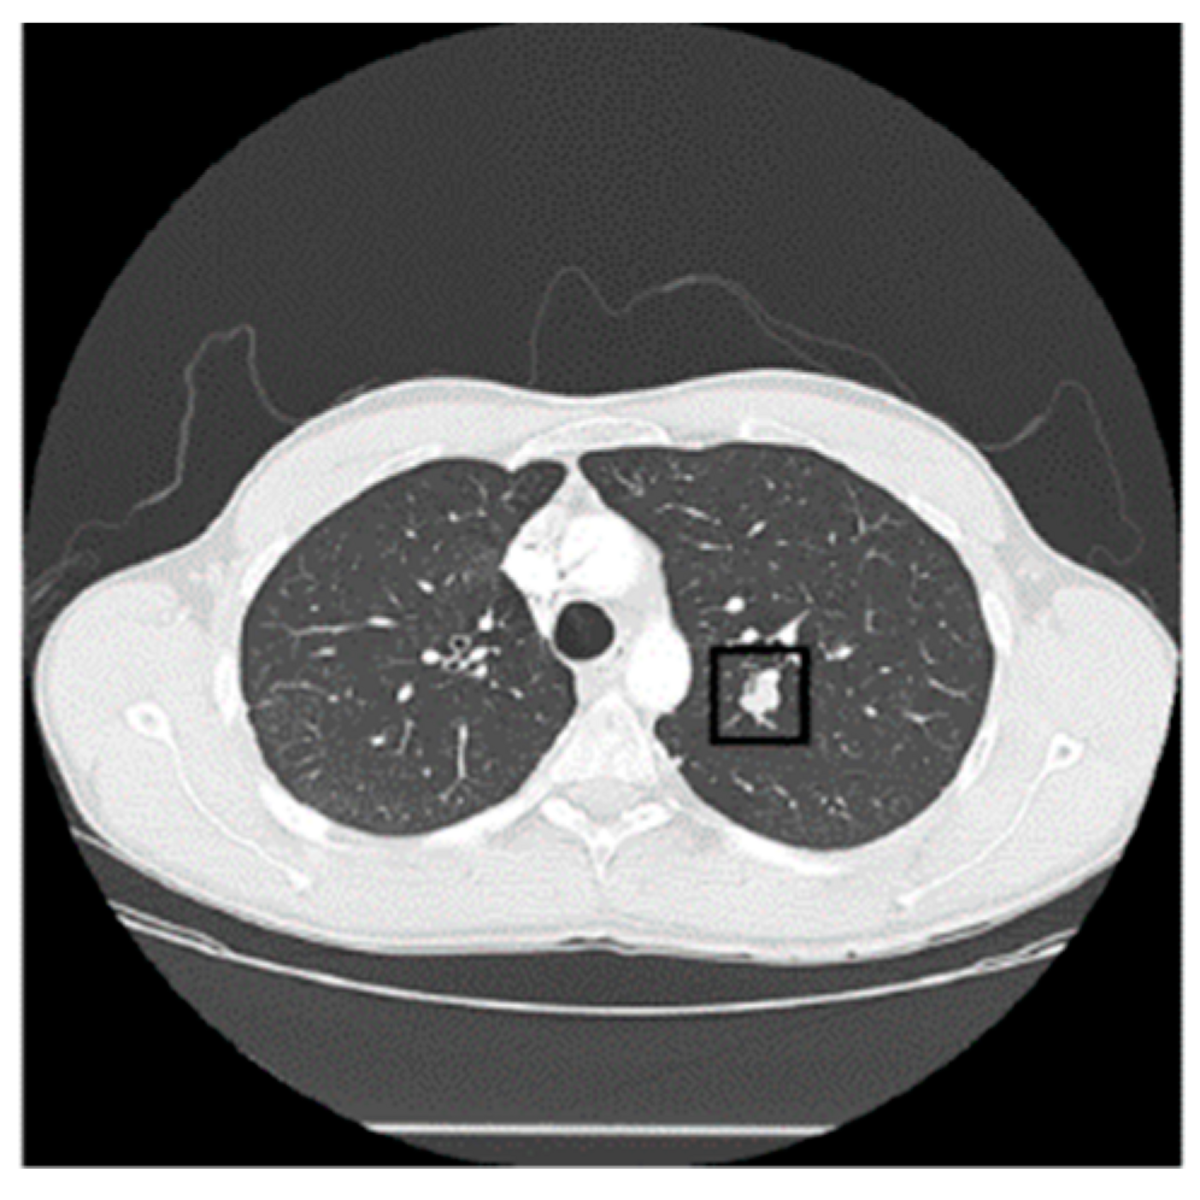

CT Lung Data for Diagnosis

Next, we got this fresh image showing how CT lung data is used for diagnosing lung cancer. The top CT lung dataset from the LIDC database is a game-changer when it comes to making accurate diagnoses and developing personalized treatment plans. This data is like a treasure trove of insights that can help us combat lung cancer like never before.

From CT Lung Data To Lung Cancer Diagnosis. (Top) CT Lung Dataset From

lung dataset lidc diagnosis